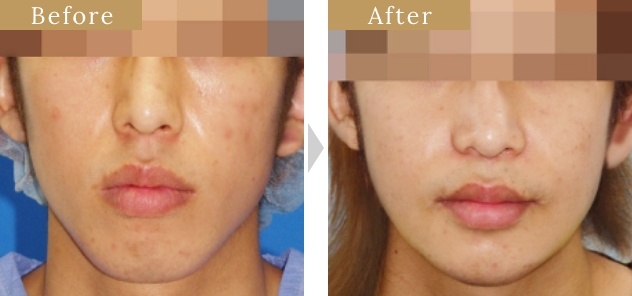

症例